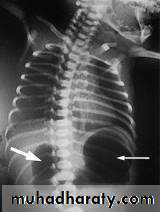

Erect abdominal X- ray: double bubble sign. If there is gas shadow beyond the duodenum, it means partial obstruction so upper GI contrast study is needed.

Double bobble sign no abdominal distension

Plain abdominal X-ray : distended stomach & proximal duodenum with little air in distal small bowel , double bubble sign , or dilated loops of bowel with multiple air-fluid levels.